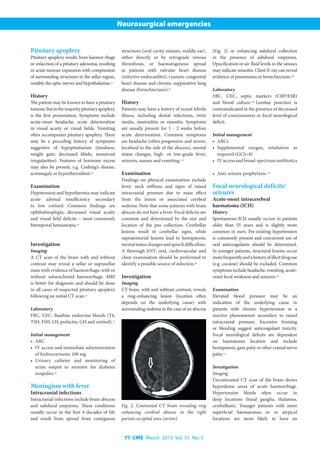

Imaging

•	 Extradural haematoma – convex,

hyperdense extra-axial lesion with or

without midline shift (Fig. 4a). An

overlying fracture is often identified.

•	 Subdural haematoma – crescent-

shaped hyperdense lesion following the

contour of the cerebral hemisphere (Fig. 4b).

Parenchymal contusions are also common.

Fig. 4a. Acute extradural haematoma:

biconvex hyperdense extra-axial lesion with

mass effect on the underlying hemisphere.

Fig. 4b. Subdural haematoma: hyperdense

extra-axial lesion following the contour of the

hemisphere.

Fig. 4c. Chronic subdural haematoma.

Hypodense extra-axial lesion with mass

effect.

•	 Chronic subdural haematoma – iso- to

hypodense collection over a hemisphere,

often with a significant midline shift

(Fig. 4c).[13]